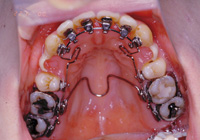

1.3D装置:

小さな顎を正しい大きさに拡大します。あるいは、奥歯の位置を固定します。

2.ブラケット:

歯に装置を接着して、ワイヤーを用いて歯並びを治します。

<表側矯正装置>

<裏側矯正装置>